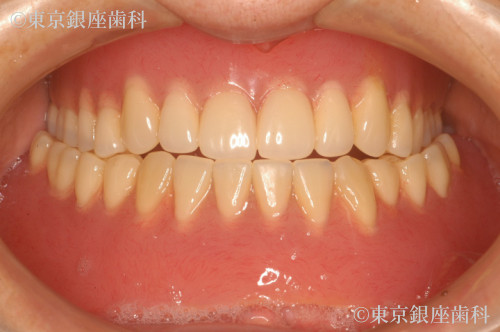

Before

総入れ歯が合わず不便を感じていたが、上下ワンデイインプラントを選択。上顎には6本の埋入と骨補強を併用し、計画通りに進行。噛み合わせも改善し自然な見た目を取り戻した。

上下ワンデイインプラント(インプラント6本+骨補強)